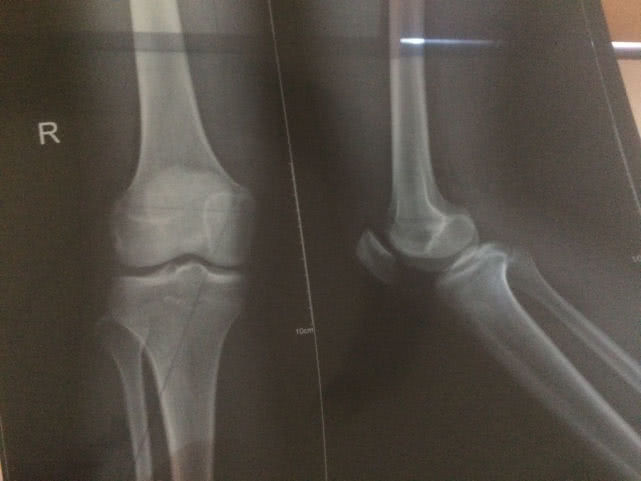

3、骨密度检查

还有部分家长特别喜欢带孩子去做骨密度检查,想通过这种方法来看看孩子能长得多高,亦或者是想看看孩子有有没有缺钙的症状。

实际上,北京大学人民医院骨科医生吴珺表示:正常孩子一般都不用做骨密度检查,除非孩子有反复骨折或是骨头出现畸变的情况,那么这时需要进行骨密度检查。

而且,目前国际上对儿童骨密度的标准值并没有给出明确规定,各个医院的检测方式也不同,因此检测出的结果也会有所不同。

如果家长们是想知道孩子还能不能再长高,那么应该去做骨垢线检查,而不是骨密度检查。至于是否有缺钙与否,家长们平时可以适当给孩子补充钙元素,等到孩子进入快速发育期时,则再多补充一些。